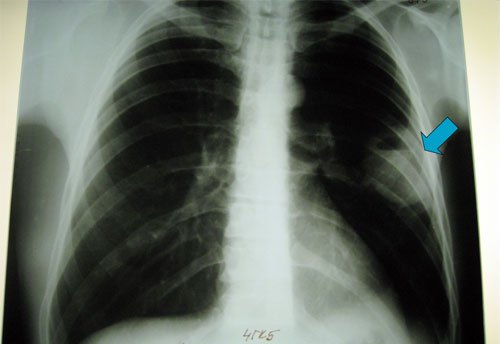

Воспаление правой верхней доли легкого хорошо обнаруживается на рентгене. Но все же пациент должен пройти не только инструментальное, но и клиническое и лабораторное обследование.

- Рентген. Проводится рентгенография в двух проекциях. На рентгенограмме обнаруживается затемнение в верхней доле и усиление легочного рисунка.

Рентгенологическая картина верхнедолевой пневмонии